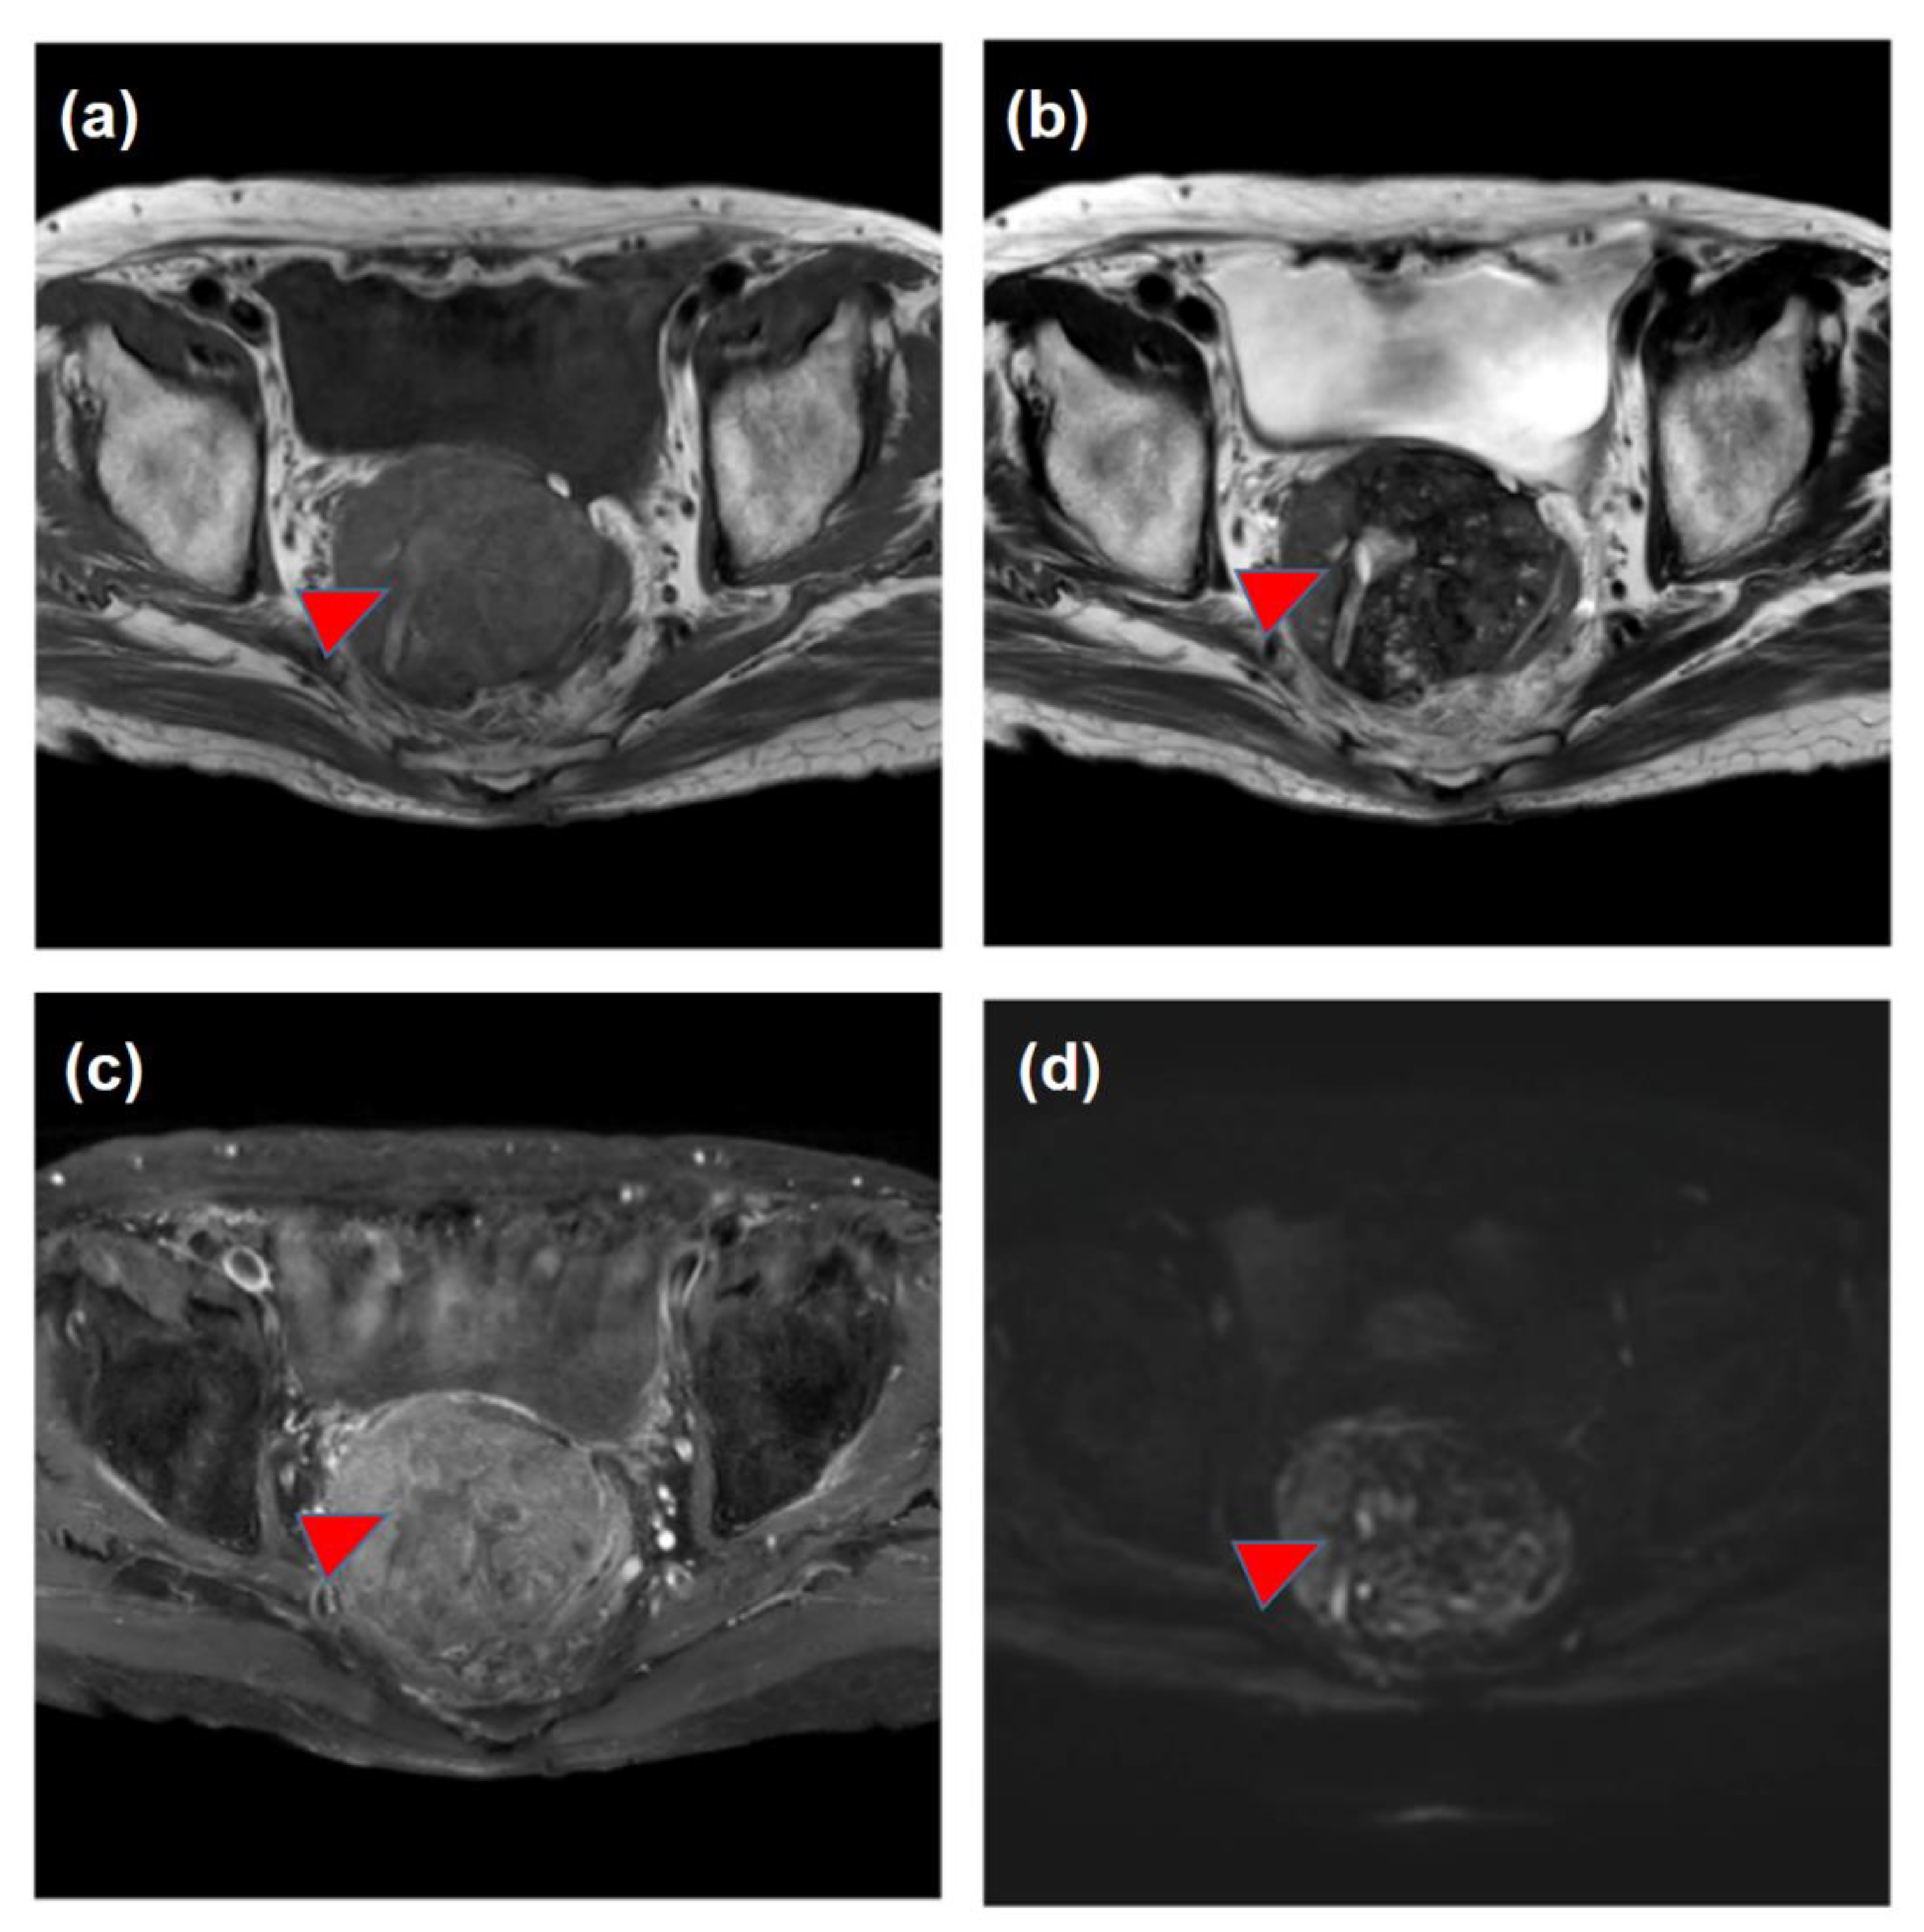

| March | Increase in the DCP and detection of the pelvic tumor Medical interview revealing mild constipation | |

| X | May | The histological diagnosis of pelvic metastasis of HCC |